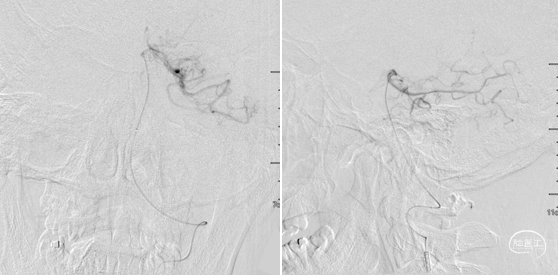

微导管造影。

支架释放后发现远段大负荷血栓影,近端狭窄,狭窄不解除,远端血栓很难清除。

碎屑栓子取出,近端狭窄影响远端栓子清除,拟近端球扩,取栓后有小缝隙,留个路图,方便导丝通过。

2.5*15mm球囊6atm 压力。

球扩后造影,远端大负荷量血栓,抽吸效果更佳,且患者局麻操作,越快越好,操作越复杂风险越大,故更换器械。